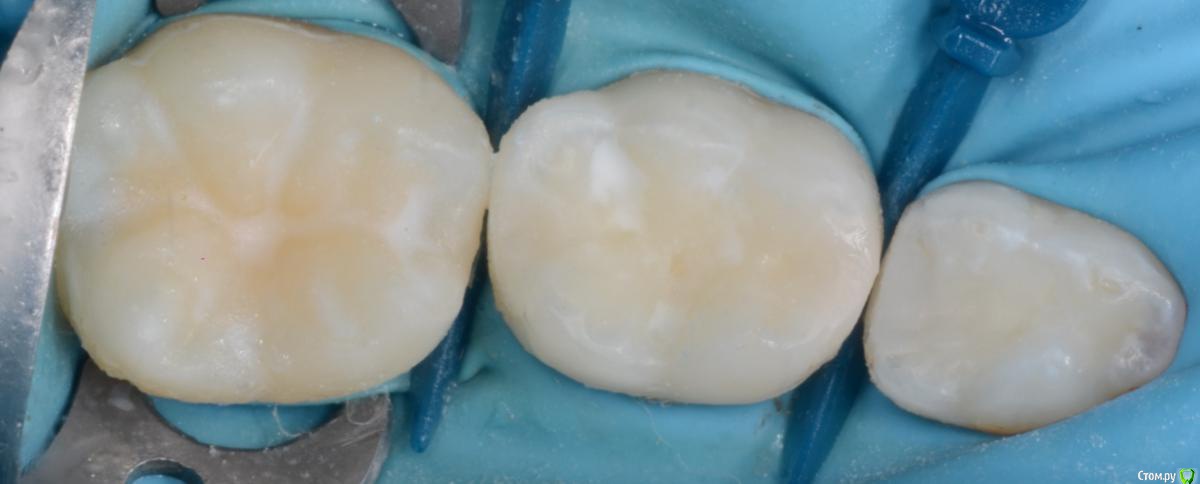

CRAZYDUCK Опубликовано 16 февраля, 2020 Автор Поделиться Опубликовано 16 февраля, 2020 Лечение обратимого пульпита 7.5 зуба . По этапам , на фото хорошо виден спонтанный гемостаз после ампутации .[url=https://radikal.ru] 2 Ссылка на комментарий

CRAZYDUCK Опубликовано 20 февраля, 2020 Автор Поделиться Опубликовано 20 февраля, 2020 Верхнее фото - зуб с герметиком . Со слов мамы перед герметизацией зуб не чистили , врач сразу нанёс герметик ( по виду похоже на жидкотекучий композит ).под жидкотекучим был кариес . Убрала жидкотекучий композит рондофлекс , препарирование и восстановление пакуемым и герметиком . 2 Ссылка на комментарий